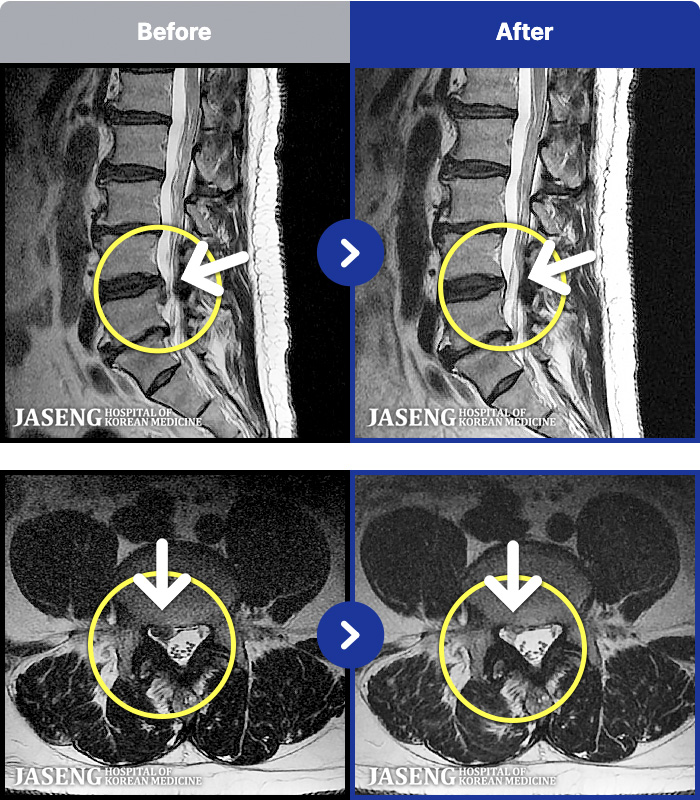

54 MRI ũ ʸ Ȯϼ.

ȯںп Ǹ ǿ ԿǾ, ο ġ ۿ Ƿ ġḦ Ͻñ ٶϴ.